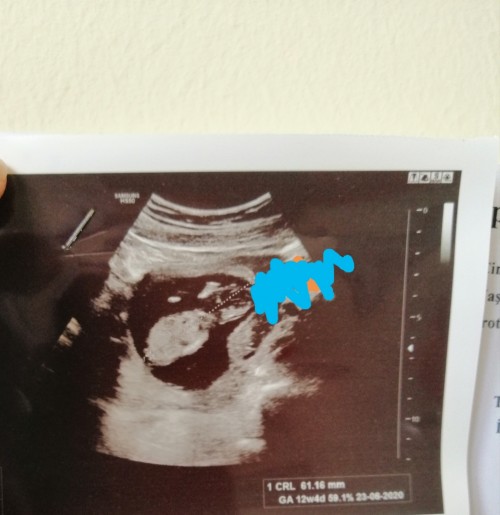

Arkadaşlar başına böyle bişey gelip sonra düzelen varmı. Kaybetmekten cok korkuyorum. Maviyle işarwtli yer rahim girişi. Rahim kanalı. Bebek çok aşağıda. Agrı sancı çok oluyor. Ayakta durmam bile yasak. Geç dönem düşük riski yada erken doğum riski dediler. Böyle olupta düzelen oldumu. 12+2